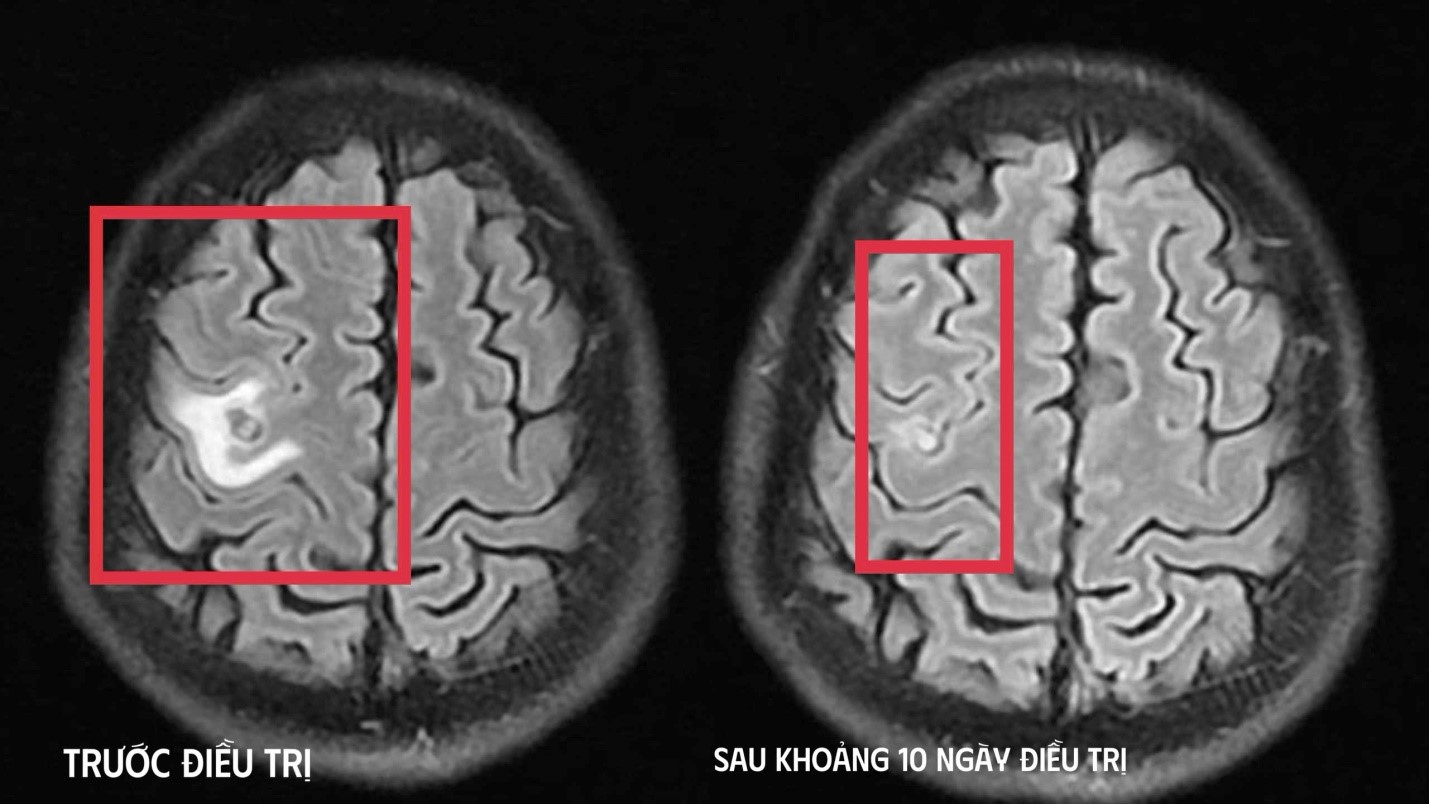

Để làm rõ nguyên nhân, các bác sĩ chỉ định chụp cộng hưởng từ (MRI) sọ não. Kết quả cho thấy có một tổn thương dạng nang nhỏ tại thùy trán trái, kích thước khoảng 11 x 7 mm, xung quanh có phù não nhẹ. Hình ảnh này gợi ý nhiều đến tổn thương do ký sinh trùng hơn là u não nguyên phát, qua đó giúp định hướng chẩn đoán theo hướng nhiễm trùng ký sinh trùng hệ thần kinh trung ương.

Sau khoảng 10 ngày điều trị tại bệnh viện, tình trạng người bệnh cải thiện rõ rệt. Các triệu chứng tê tay trái hoàn toàn biến mất, không còn xuất hiện cơn co giật, người bệnh không còn đau đầu hay chóng mặt, toàn trạng ổn định. Bệnh nhân được cho ra viện và tiếp tục điều trị ngoại trú đủ liệu trình kéo dài 4 tuần theo hướng dẫn của bác sĩ.

Khi tái khám gần một tháng sau, kết quả chụp cộng hưởng từ sọ não cho thấy tổn thương dạng nang thu nhỏ rõ rệt, tình trạng phù não xung quanh giảm đáng kể, không còn dấu hiệu tiến triển. Kết quả này cho thấy người bệnh đáp ứng tốt với điều trị nội khoa. Trên cơ sở đó, bệnh nhân tiếp tục được chỉ định thêm một đợt thuốc củng cố và theo dõi lâu dài nhằm phòng ngừa nguy cơ tái phát.